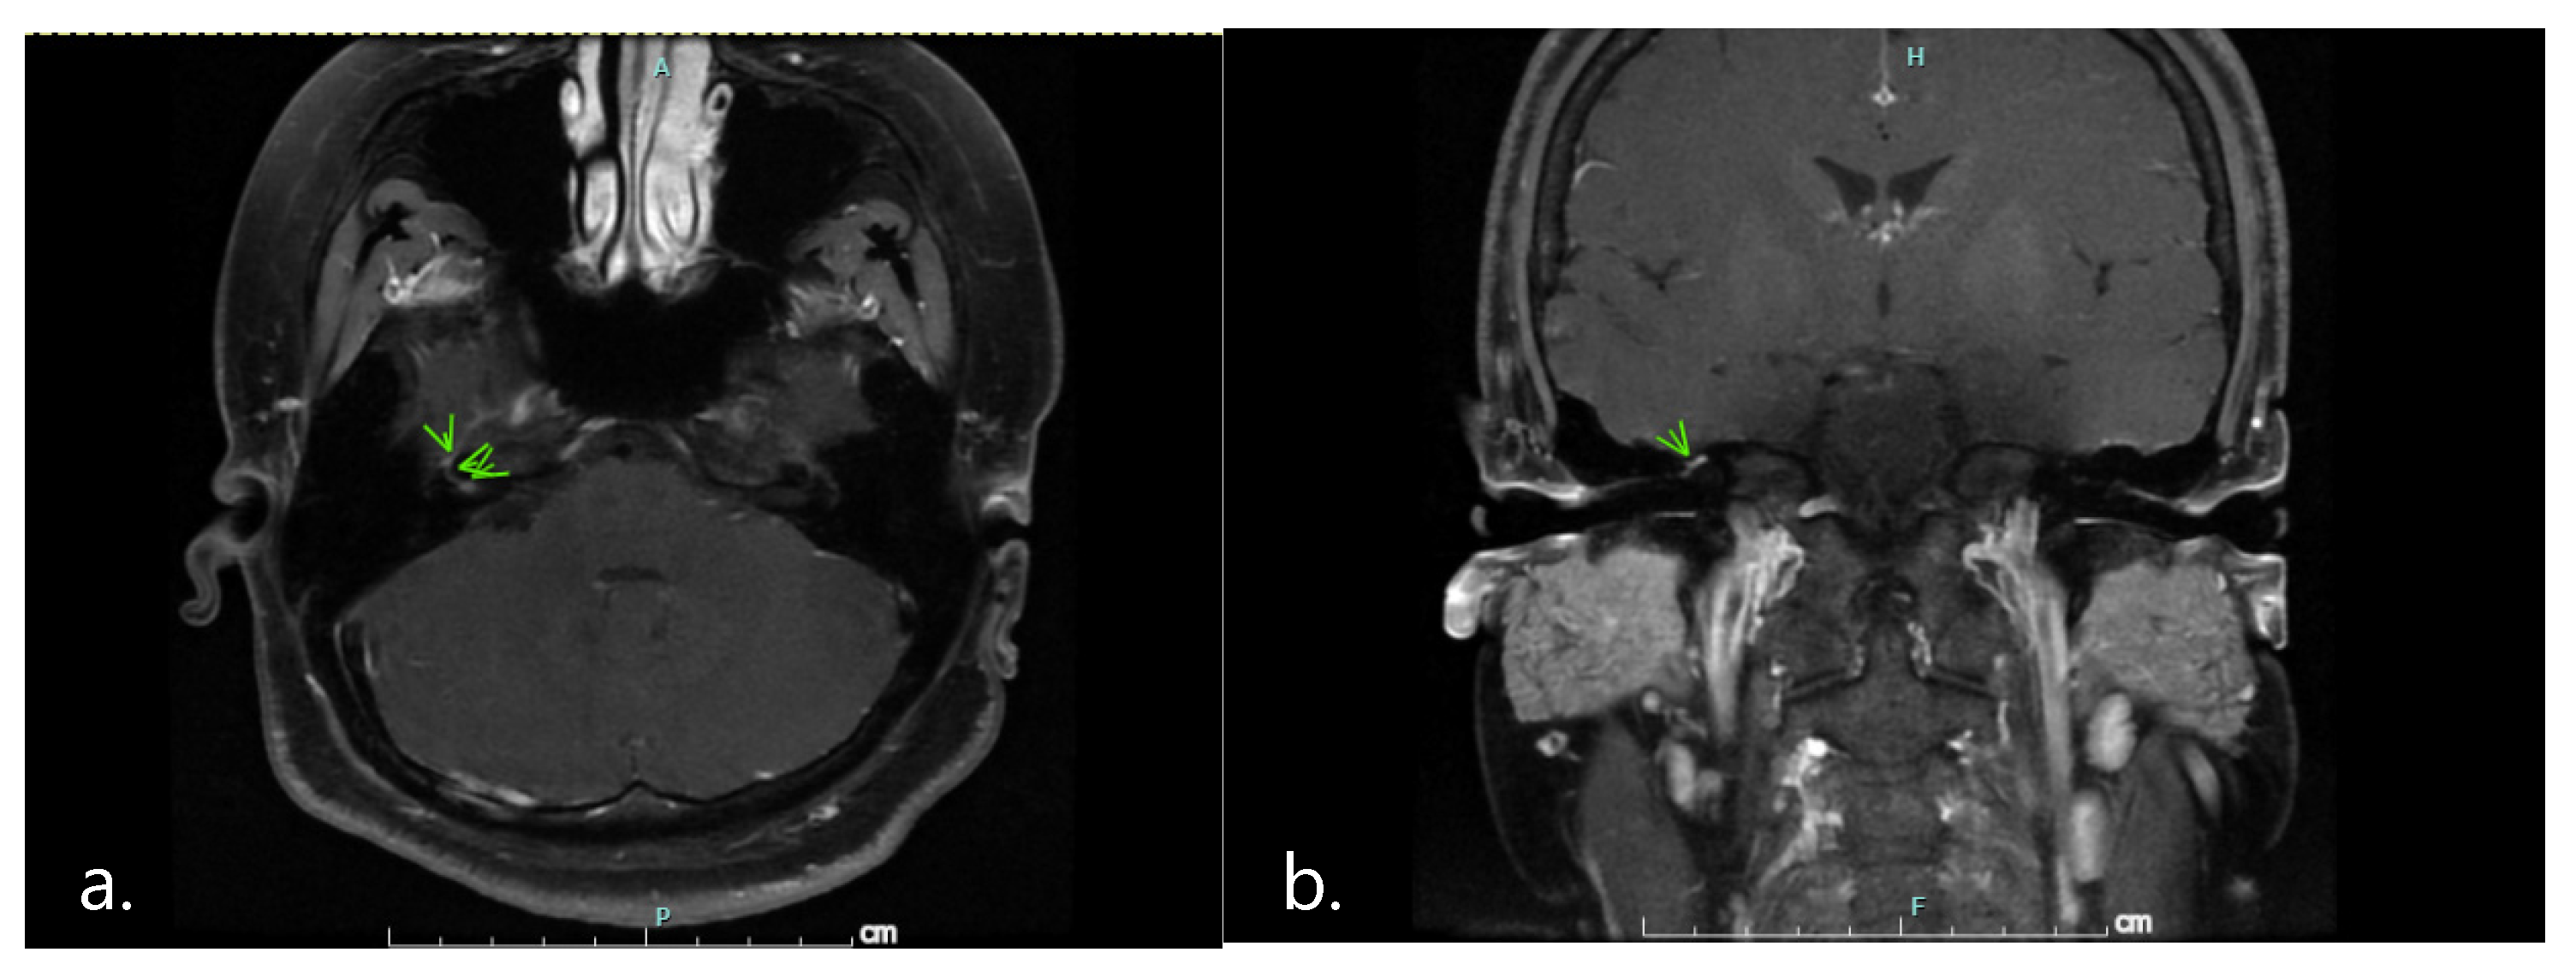

2. Case Presentation